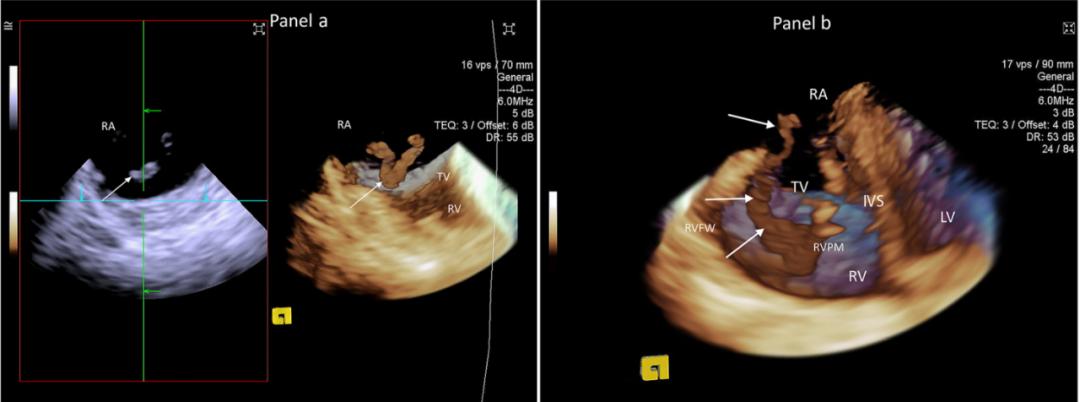

(2) 心腔内三维超声技术

心腔内超声与血管内超声不同,不需要专用的超声成像仪,但其专用探头类似于血管内超声导管。将微型的换能器安装在心导管的尖端,再经外周血管送入心腔,换能器发射声波,将接收到的回波经计算机处理后形成超声图像[6]。

图2. 心腔内三维超声技术心脏图像[7]

[7] Three-dimensional intracardiac echocardiography and pulmonary embolism. Cardiovasc Ultrasound. 2020 Aug 20;18(1):36. doi: 10.1186/s12947-020-00220-3. PMID: 32819376; PMCID: PMC7441699. Yastrebov K, Brunel L, Paterson HS, Williams ZA, Bannon PG.